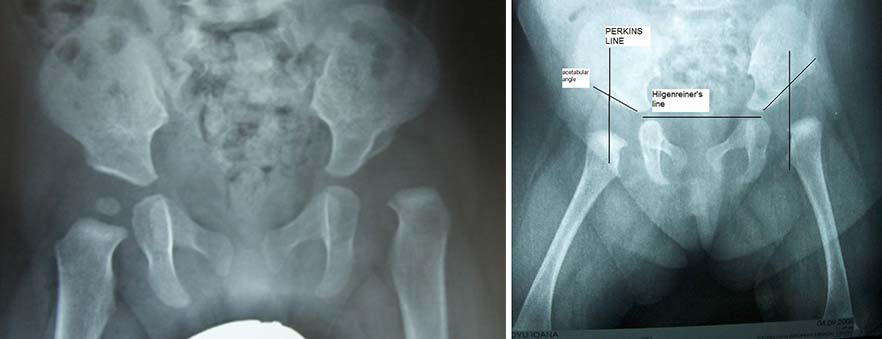

Εικόνα Ακτινολογικός έλεγχος αμφοτερόπλευρου εξαρθρήματος ισχίου

Η διάγνωση της δυσπλασίας του ισχίου μετά από τον κλινικό και υπερηχογραφικό έλεγχο, καλό είναι να καταγράφεται και με ακτινολογική εξέταση.

Η ακτινολογική εξέταση στην νηπιακή και παιδική ηλικία αξιολογεί ποικιλία παραμέτρων. Μετράται η κοτυλιαία γωνία, το ποσοστό κάλυψης της κεφαλής, η γωνία CE (η γωνία που σχηματίζεται από την κάθετο που περνά από το κέντρο της κεφαλής και την ευθεία του σχηματίζεται από την ένωση του κέντρου της κεφαλής με το άνω έξω χείλος της κοτύλης), δείκτες που χρησιμοποιούνται κυρίως στην αξιολόγηση της θεραπευτικής αντιμετώπισης του δυσπλασικού ισχίου. ( ταξινόμηση κατά Severin).

Έχει μεγάλη σημασία, όπως και στο υπερηχογράφημα, έτσι και στον ακτινολογικό έλεγχο να γίνεται η σωστή τοποθέτηση και ακινητοποίηση του βρέφους, ώστε να αποφεύγεται η κλίση της πυέλου, που οδηγεί σε λανθασμένα συμπεράσματα.